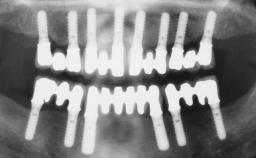

Conventional Loading of Eight Implants in the Maxilla and Final Restoration with a Full-Arch Gold-Ceramic FDP

| # of Implants | 8 |

| SAC Level | Complex |

| Defining Characteristics | Fully edentulous upper jaw to be rehabilitated with four or more implants |

| Bone Volume | Deficient vertically or deficient vertically AND horizontally |

| Defining Characteristics | Fully edentulous upper jaw to be rehabilitated with an implant-borne fixed dental prosthesis |